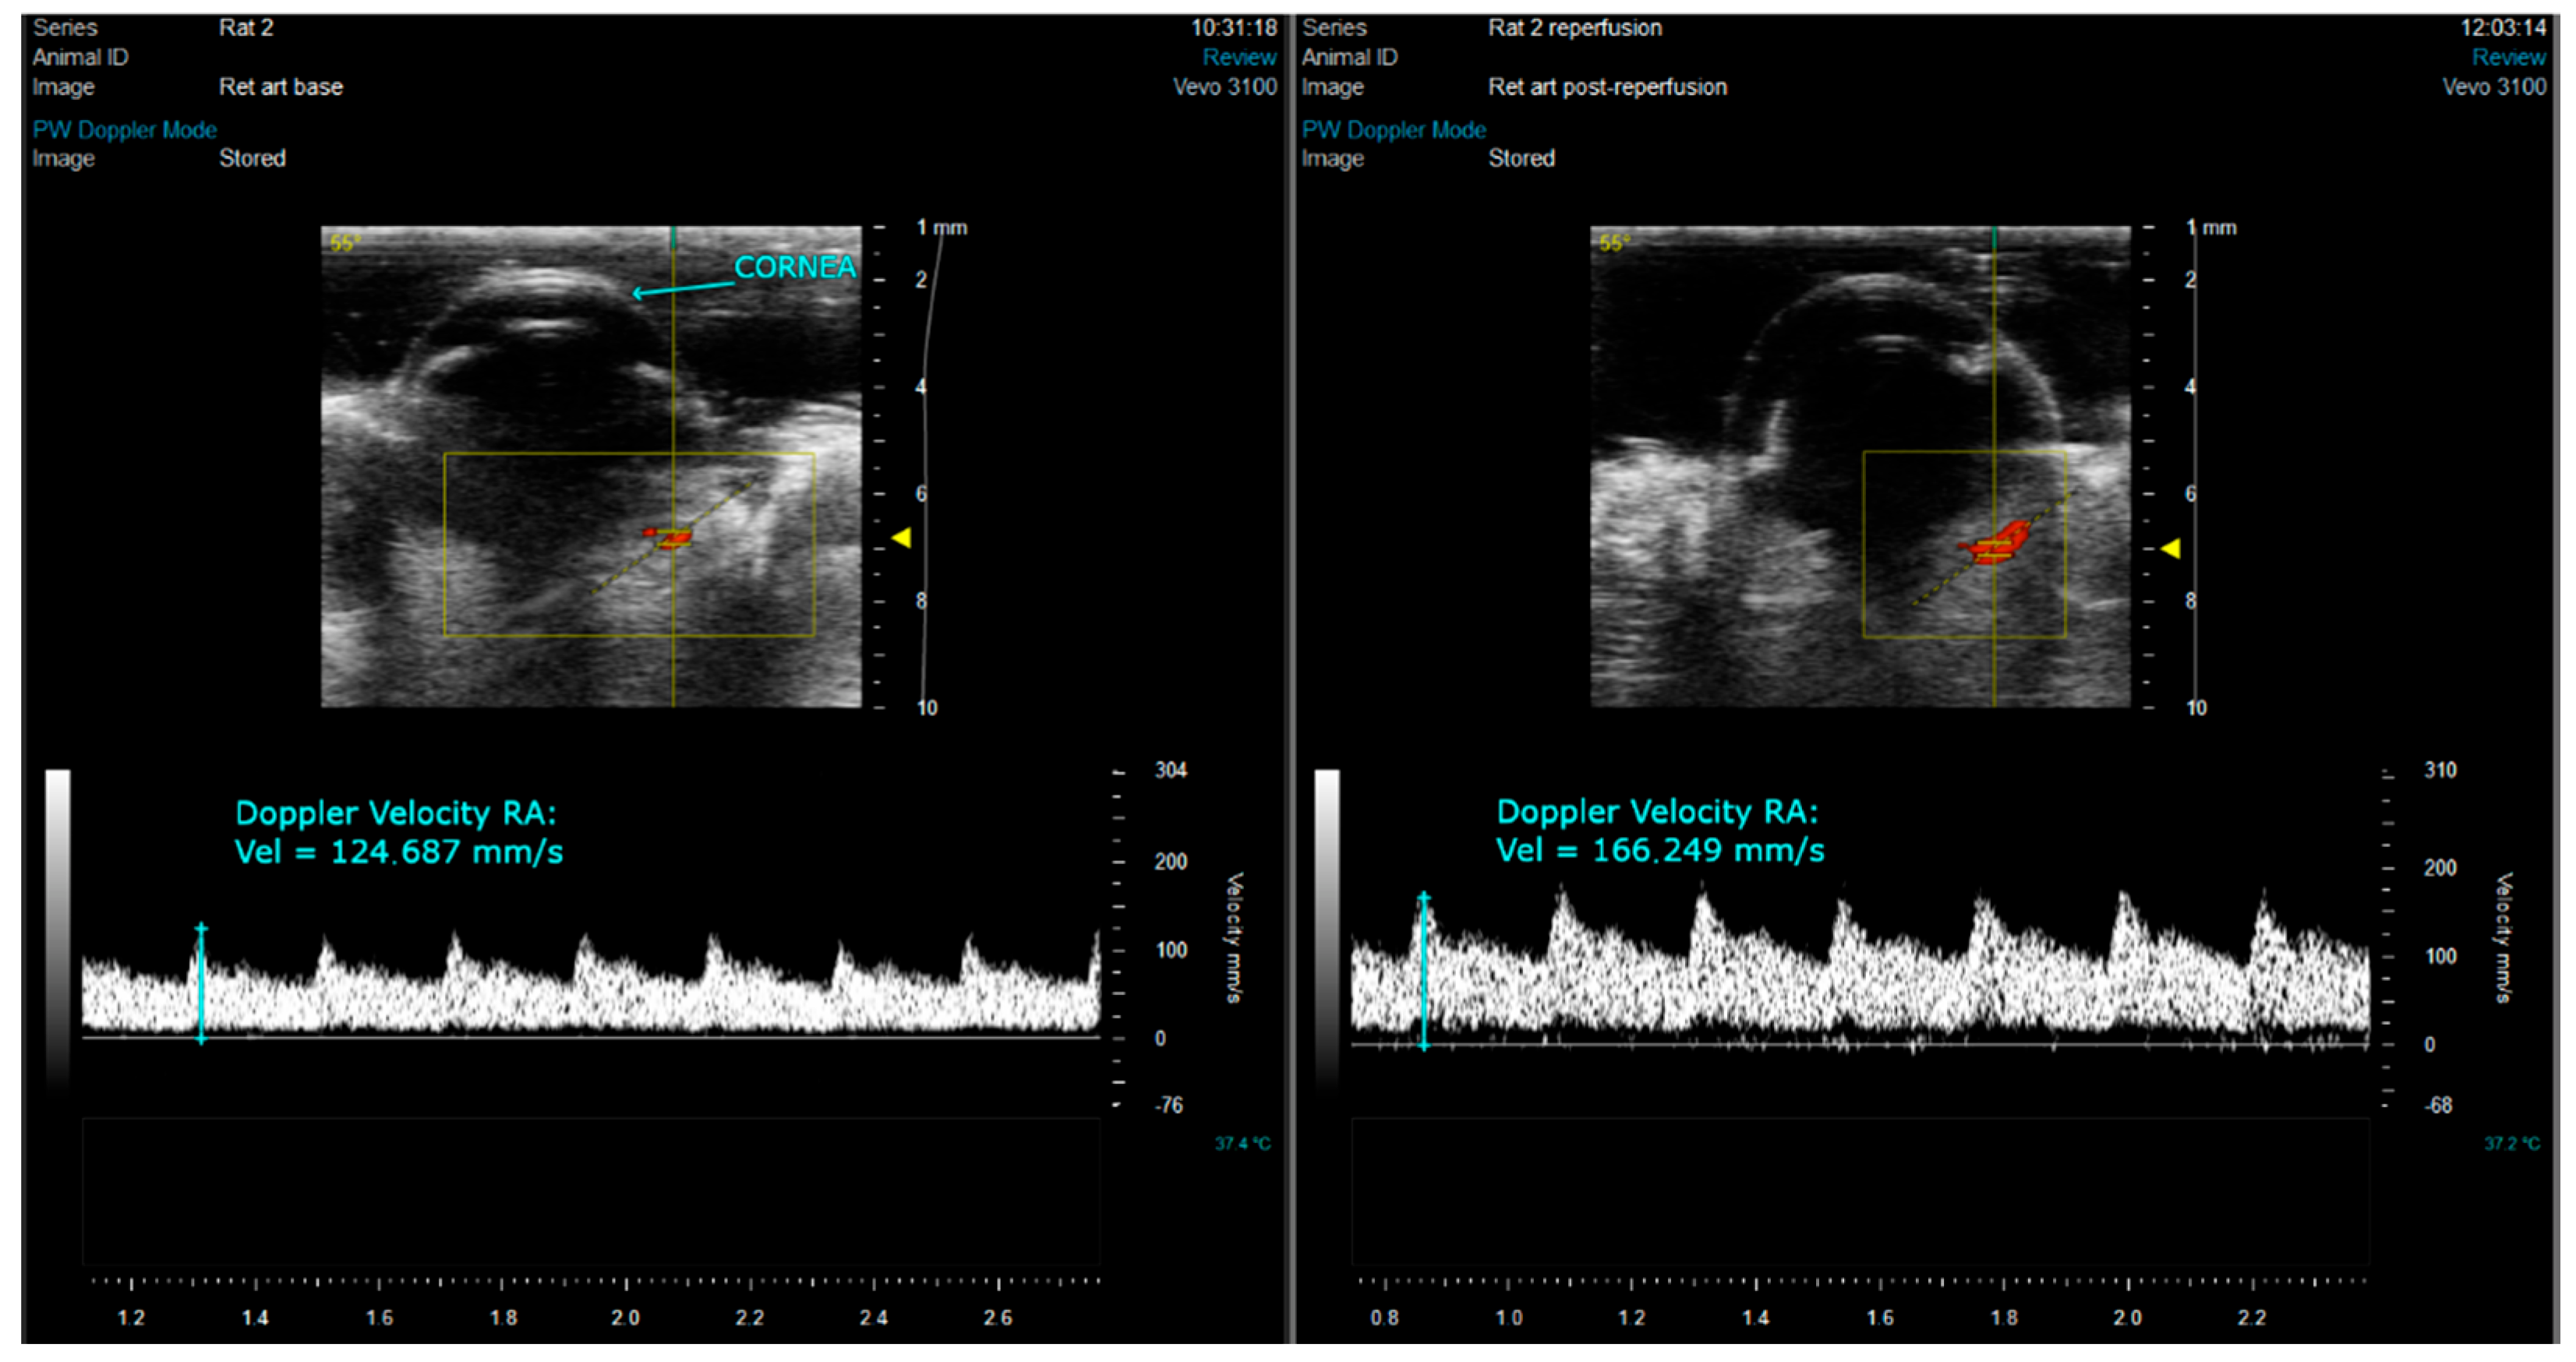

2.3. Ocular Echography

3.1. Ocular Ultrasound